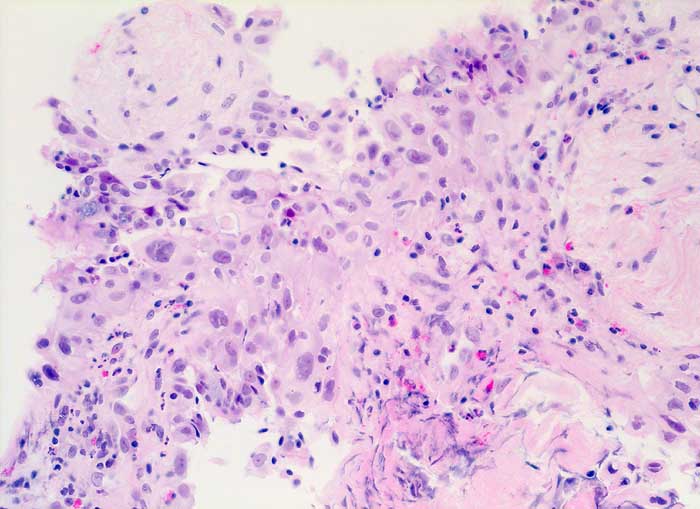

PathoPic ID 6361 - strahleninduzierte Kernatypien

strahleninduzierte Kernatypien

Therapiefolgen

Bronchus

Lunge, Mediastinum mit Thymus

Ausgeprägte Kernpolymorphie und Kernvergrösserung des respiratorischen Epithels bei erhaltener Kern-Zytoplasmarelation.

NSCLC neoadjuvante Therapie

Histologie

200